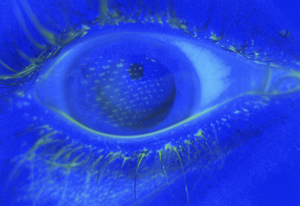

- Fluorescein Exam

- Apply 1 gtt of flourescein or utilize strip with anesthetic

- Use Wood's Lamp or Slit Lamp with colbalt blue light

- Fluoresceine will fill corneal defects and glow

- Multiple vertical abrasions suggests foreign body embedded under the upper lid

- Fluorescein Examination

- Seidel sign (streaming of fluorescein) indicates penetrating trauma

- Branching/Dendritic pattern suggests possible Herpes Zoster Ophthalmicus